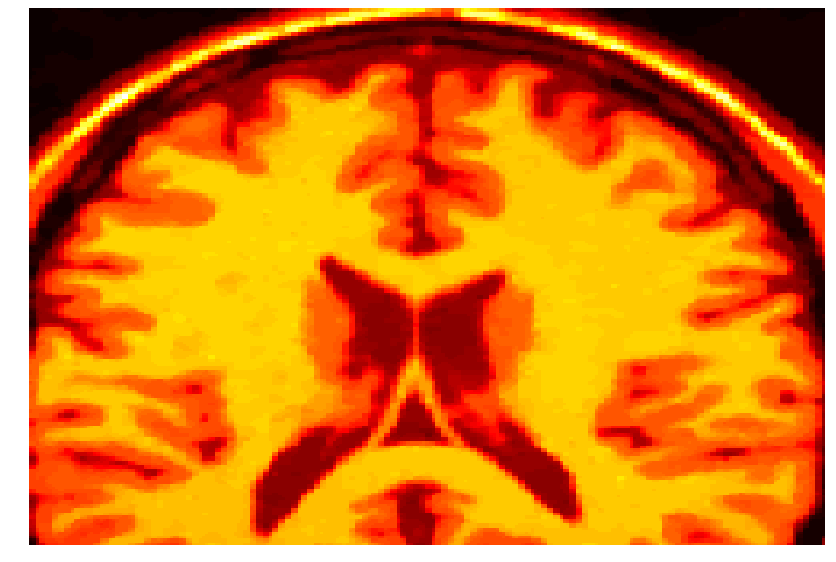

4.2 Magnetic resonance imaging

Gaussian noise images typically arise within the framework of magnetic resonance imaging (MRI). The challenge in this case consists in training the machines so that a clearer image is obtained. The magnetic resonance images seem to be the natural choice for our methodology, since a training set of images is often at hand.

For such a training set we consider the solution of problem (40). In Figure 2 the noisy images together with the final optimized ones for a brain scan are shown. For this experiments a mesh step size of was considered. The Tikhonov regularization parameter took the value , while the Huber regularization parameter was chosen as .

With this values, the optimal parameter value for the MRI image with 3% of noise was . When the noise in the image was of 9%, the computed optimal weight was .